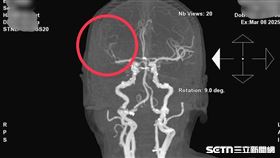

納豆腦出血手術!醫曝這5種人危險

藝人納豆驚傳腦出血住院,各界正在集氣希望他平安康復。...